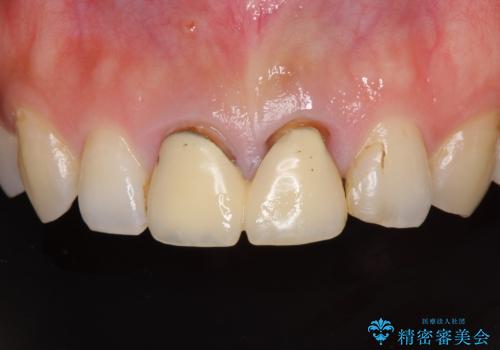

- 前歯のクラウンが着色により不自然な色となっていることを気にして来院された患者様です。

クラウンと歯の縁も合っておらず、汚れが溜まりやすい環境であったため、前歯2歯のクラウンをオールセラミッククラウンにて再補綴することとしました。